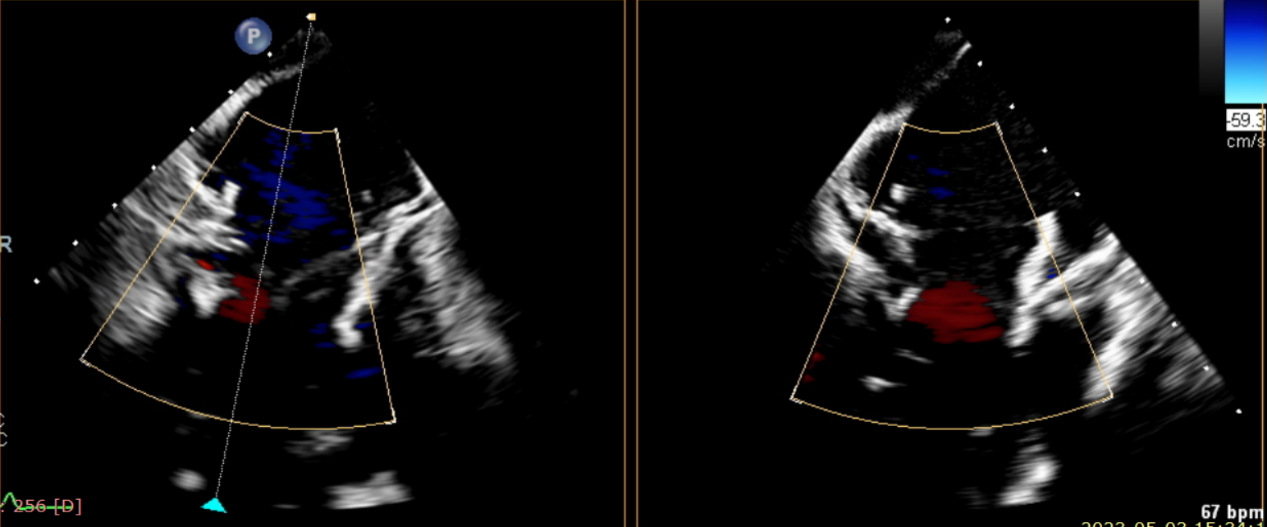

術(shù)前超聲提示大量三尖瓣反流

術(shù)中輸送器在超聲引導(dǎo)下調(diào)整位置

術(shù)后超聲提示無瓣周漏